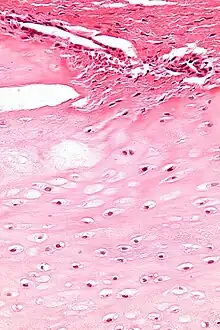

| Enchondromas are present in Maffucci syndrome | |

Maffucci syndrome is a very rare disorder in which multiple benign tumors of cartilage develop within the bones (such tumors are known as enchondromas).[1] The tumors most commonly appear in the bones of the hands, feet, and limbs, causing bone deformities and short limbs.[1]

The enchondromas affect the extremities and their distribution is asymmetrical. The most common sites of enchondromas are the metacarpal bones and phalanges of the hands. The feet are less commonly affected.[4] Disfigurations of the extremities are a result. Pathological fractures can arise in affected metaphyses and diaphyses of the long bones and are common (26%).

The risk for sarcomatous degeneration of enchondromas, hemangiomas, or lymphangiomas is 15–30% in the setting of Maffucci syndrome. Maffucci syndrome is associated with a higher risk of CNS, pancreatic, and ovarian malignancies.[5] Multiple enchondromas may present in three disorders: Ollier disease, Maffucci syndrome, and metachondromatosis. It is important to make the distinction between these diseases, particularly Ollier disease and Maffucci syndrome. Ollier disease is more common than Maffucci syndrome, and presents with multiple enchondromas often in a unilateral distribution. However, hemangiomas and lymphangiomas are not seen in Ollier disease.[6] Metachondromatosis demonstrates autosomal-dominant transmission and presents with both multiple osteochondromas and enchondromas.